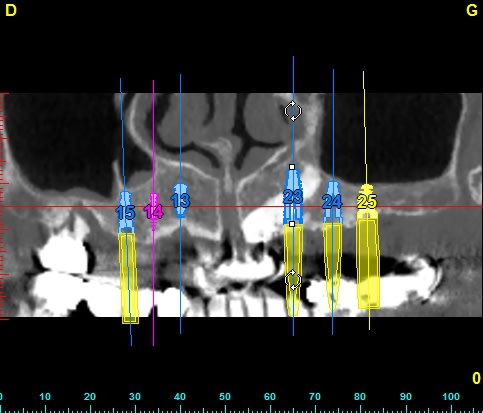

patiente de 80ans, canine incluse depuis donc pas mal de temps. ATCD de prothese amovible depuis 15ans. Je crains que sa canine soir hyper ankylosé et je me propose donc d'implanter au travers.

Canine coupe vestibulo linguale b2loil - Eugenol

comment tu fais ton forage

comment tu tarode

comment tu gére l'espace entre l'implant et le reste de dent

comment tu fais l'endo de la canine une fois que tu seras passé a travers

le problème c'est que le logiciel 3D ne réfléchit pas il donne juste de belles images

C'est bien ma crainte mais j'ai plusieurs questions : les forets antogyr ne risquent-ils pas de déraper au contact de la racine de 13 ?

Y a-t-il bien une sidération nerveuse de 13 qui m'évite tout tt endo de 13 (impossible en laissant 13 en place d'ailleurs)?